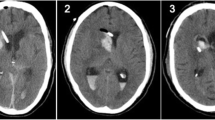

Technique used in human. A Placement of the catheter guide on the planned entry point on the scalp. B Electric power drill and catheter guide assembled. Note that the tip of the drill projects 15–20 mm beyond the bottom of the base ring of the catheter guide. C Insertion of the electric power drill through the tube of the catheter guide. D Insertion of the ventricular catheter through the pre-drilled burr hole with CSF flow

In concordance with the previously calculated parameters, the entry point is marked, and spray or wipe disinfected. A 5–10-mm straight skin incision is performed. The Thomale Guide is assembled with a 3.1-mm inner diameter tube, fastened with the locking nut to obtain the predetermined angulation and placed on the entry point. The disposable battery-powered 2.7-mm diameter drill (Phasor Health, Houston, USA) with an anti-plunge drill stop is introduced through the catheter guide until the tip reaches the skull bone, while the catheter guide is sturdily pressed with one hand onto the skin surface. A burr hole is made with the electric drill, and the catheter guide is removed out of the surgical field. The cranial dura mater is perforated with a standard 14-gauge venous cannula if needed. A standard silver impregnated EVD catheter with an outer diameter of 2.8 mm (VentriGuard®, Neuromedex, Hamburg, Germany) or a ventricular catheter with an outer diameter of 2.5 mm (Ventricular Catheter, Christoph Miethke, Potsdam, Germany) is inserted and guided through the pre-drilled burr hole to the calculated depth, indicated by the printed on scale, and then the guide wire is removed (Fig. 2). The ventricular catheter is tunneled for at least 4 cm from the insertion point subcutaneously, sutured to the skin and connected to an external CSF drainage system (VentrEX®, Neuromedex, Hamburg, Germany).

The patient is in supine position on an intensive care unit (ICU) or regular hospital bed in 30–50° of head elevation. For stabilization of the head against the bed, an emesis basin or donut head pad is placed beneath it and fixed with a conventional tape.